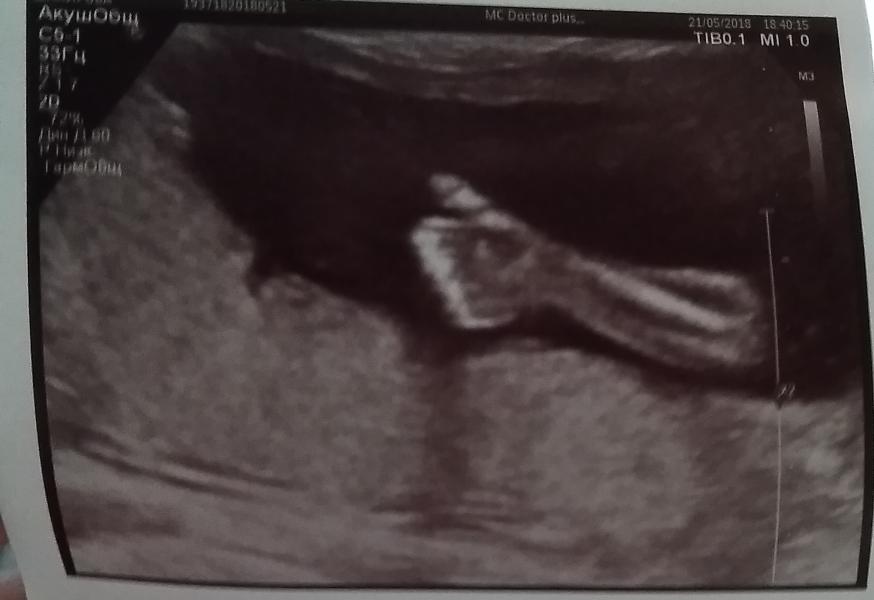

Вот мы и сходили на 1 часть 2 скрининга (я наблюдают в платной клинике и здесь 2 скрининг идёт в 2 этапа с разницей 2-3 недели, оба раза УЗИ,смотрят абсолютно все параметры с разницей 2-3 недели)

На УЗИ мы были долго наш малыш все не хотел даваться этой тетеньке, все прятался от нее или ускальзывал. Показывал нам руки, ноги, спину, попу, голову.😂😂😂

Мы детально рассмотрели лицо, затылок, ноги, руки.

С трудом рассмотрели ❤️, всё отлично, пороков нет.

Но я лично не увидела самого главного кто у на...